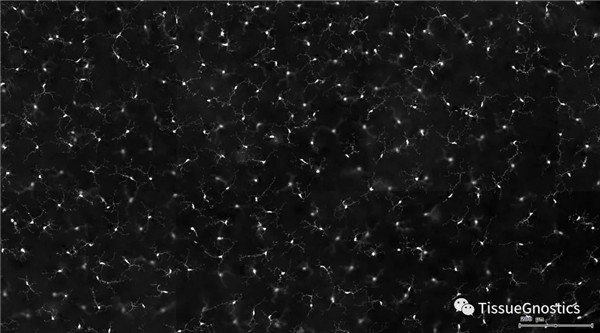

視網膜熒光樣本中小膠質細胞胞體、神經纖維識別、血管識別、血管斑點識別、神經元與血管的距離分析。

1. 利用TissueFAXS系統(tǒng)進行玻片熒光的全景掃描。

3. 根據FITC通道識別神經胞體并篩選出細胞胞體(細胞核識別算法)。

單通道灰階圖(↑:FITC,↓:Texa Red)